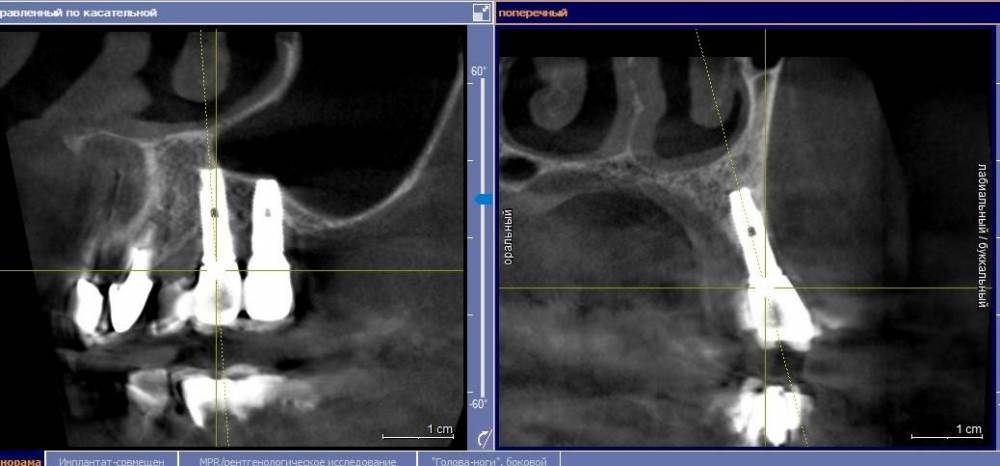

Ponchik Опубликовано 23 ноября, 2021 Поделиться Опубликовано 23 ноября, 2021 Заказ от начальства(ортопеда). Пациентка направлена ко мне со словами: вам сейчас косточки подсыпят, десенки пришьют и всё ок. Инересует второй сегмент, остальные и так ок. Работе всего пара лет. Делал не я. Импланты альфа-био. Прикреплёнки нет нигде. Всё хлюпает. Второй сегмент - я за удаление имплантов, через два месяца сунус+кость+мембрана(титан или полужесткая), через полгода 24, 26 импланты. Через 3 месяца мягкотканные дела, ещё через пару месяцев замаячит протезирование. (если всё остальное сложится) Как "подлепить" десну не снимая ортопедии, за два-три визита, хотя бы прикрыть витки? Я не знаю. Приму любой совет. Ссылка на комментарий

АнтонТЛТ Опубликовано 23 ноября, 2021 Поделиться Опубликовано 23 ноября, 2021 Витки заполировать и провести медикаментозную обработку. Но лучше конечно удалить такие имплантаты. Хорошо что в вашем случае нет зубов дистально) Ссылка на комментарий

Ponchik Опубликовано 23 ноября, 2021 Автор Поделиться Опубликовано 23 ноября, 2021 Боюсь если я так сделаю, то как минимум дистальный улетит. Ссылка на комментарий